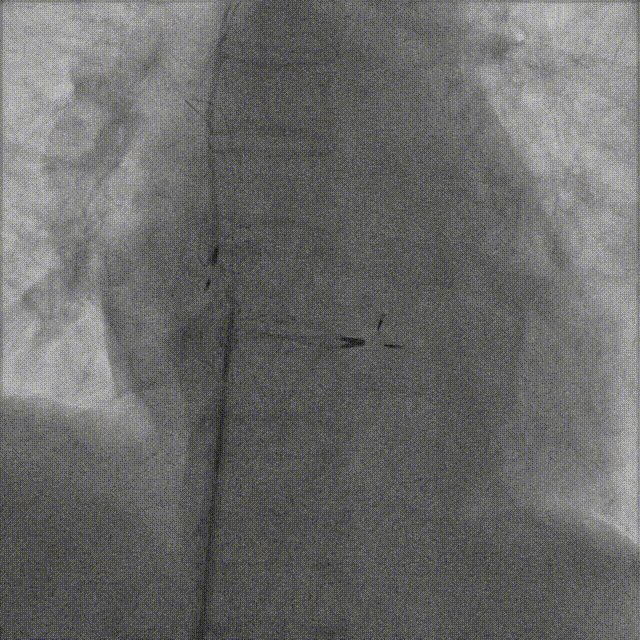

随后经右股静脉穿刺,使用血管内异物圈套器成功抓捕并拔除3根实心电极导线。术程顺利,患者安返病房。

血管内异物圈套器抓捕电极导线